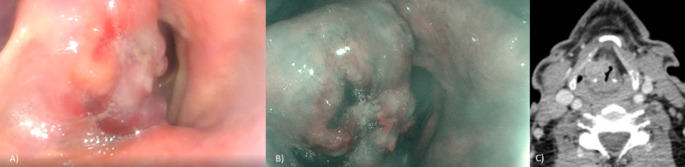

Visualization of the right hemilaryngeal lesion using videolaryngoscopy.Fig 1. Videolaryngoscopy of the lesion in right hemilarynx.1

1. Maglione, Maria Grazia et al. "Rare Primitive Lung Adenocarcinoma in Larynx: A Case Report." Indian journal of otolaryngology and head and neck surgery 76,6 (2024): 5925-5929. Distributed under Open Access license CC BY 4.0, without modification.